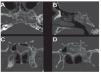

Caso clínico: Varón de 42 años de edad con paresia del VI par craneal derecho y estudios de imagen mediante resonancia magnética y tomografía computarizada craneales sugestivos de displasia fibrosa esfenoclival. Se lleva a cabo un abordaje endonasal expandido transpterigoideo completamente endoscópico, obteniéndose una amplia descompresión de las estructuras vasculonerviosas de la base del cráneo. Durante el procedimiento se utiliza neuronavegación y el canal vidiano como referencia anatómica fundamental de la carótida en su segmento lacerum.

Case report: A 42-year-old male with right sixth cranial nerve palsy. Cranial MRI and CT showed a central skull base lesion with diagnostic suspicion of FD. Patient underwent a full endoscopic transpterygoid EEA, achieving a wide skull base neurovascular decompression. Neuronavigation and the vidian canal landmark resulted mandatory during intraoperative procedure.